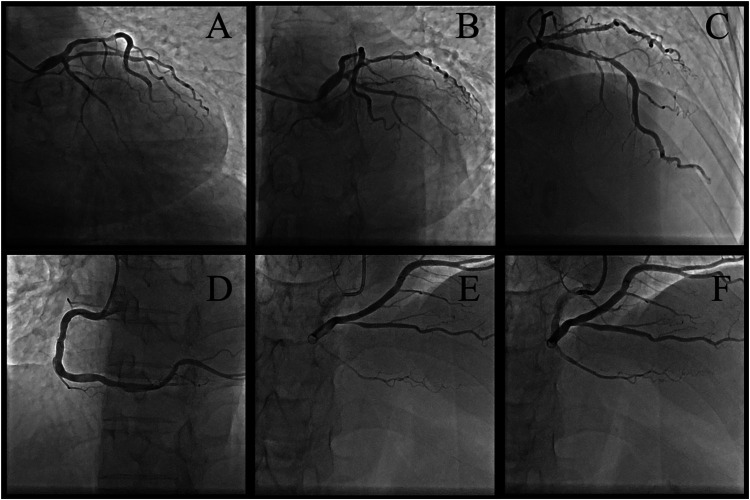

Case summary: A 51-year-old male with immune nephritis, chronic kidney disease (CKD), and poorly controlled hypertension presented with unstable angina. Coronary angiography revealed multivessel disease [70% stenosis in the proximal left anterior descending artery (LAD) and 90% in the posterior descending artery]. Initial treatment included angioplasty with a drug-coated balloon in the posterior descending artery, dual antiplatelet therapy, statins, and prednisone (10 mg/day). Seven months later, after self-reducing GCs to 5 mg/day, he suffered an acute myocardial infarction due to LAD plaque rupture, confirmed by optical coherence tomography (OCT) showing fibrolipid-rich plaques, deep calcifications, and minimal lumen area (0.67 mm2). Emergency stenting was performed to stabilize the patient, with no recurrence at 3-month follow-up.